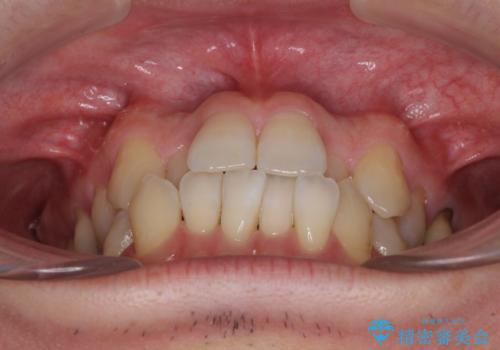

前歯のクロスバイト 目立たないワイヤー装置で矯正治療

- 前歯のクロスバイトを改善したいとのことで来院された患者様です。

マウスピース矯正では前歯の神経への負担が大きいことを懸念され、ワイヤー装置による矯正治療を行うこととしました。

舌の突出癖が認められたため、デコボコ改善に伴い前歯が前突する可能性があったため、舌のトレーニングをしっかりと行うよう指導しながら治療を進めることとしました。